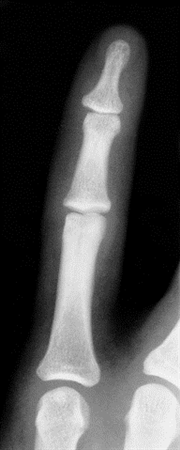

Phalanx Dislocations

• Phalanx Dislocations are common traumatic injury of the hand involving the proximal interphalangeal joint (PIP) or distal interphalangeal joint (DIP).

• Diagnosis can be made clinically and are confirmed with orthogonal radiographs.

• Imaging

• Radiographs

• recommended views

• AP

• lateral

• oblique

• findings

• V sign

• results from dorsal joint widening

• indicates subtle subluxation